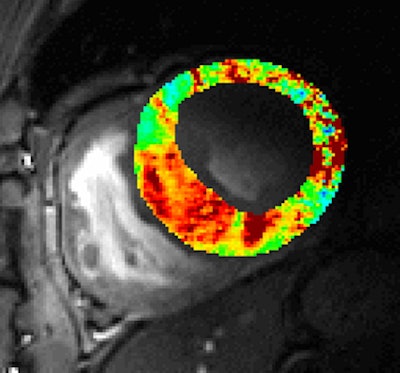

Another area of clinical interest is cardiac UHF-MR. We showed at 7T that prolongation in the myocardial relaxation time T2* is a marker for hypertrophic cardiomyopathy and provides new insights into myocardial microstructure.